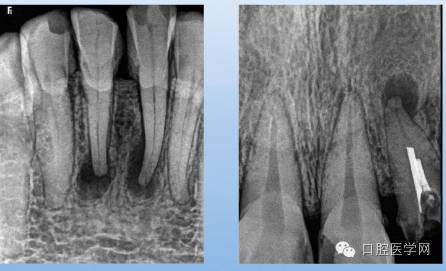

X线表现:骨小粱增粗、变密,骨髓腔变窄、消失;

硬化区与正常组织无明显分界;

牙周膜间隙增宽,根尖无增粗。

临床表现:多无症状,发现于拔牙困难或X片

X线表现:牙根粗大;牙周膜间隙变窄或消失。